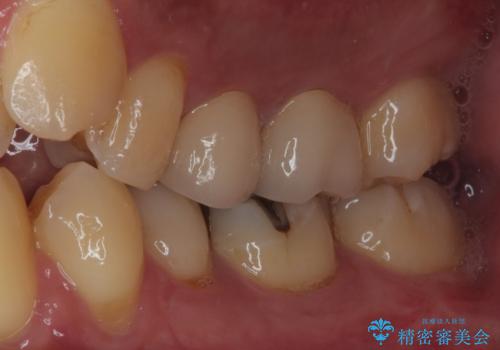

生活歯髄療法を行い状態が安定していることを確認してからオールセラミッククラウンによる補綴治療を手前の銀歯を含め2本同時に行いました。

生活歯髄療法は、むし歯が神経の近くまで進行している場合でも、できる限り神経を残すことを目指す治療法です。

従来であれば神経を取る必要があるケースでも、特殊な材料を使用することで神経を保護し、歯の寿命を延ばせる可能性があります。